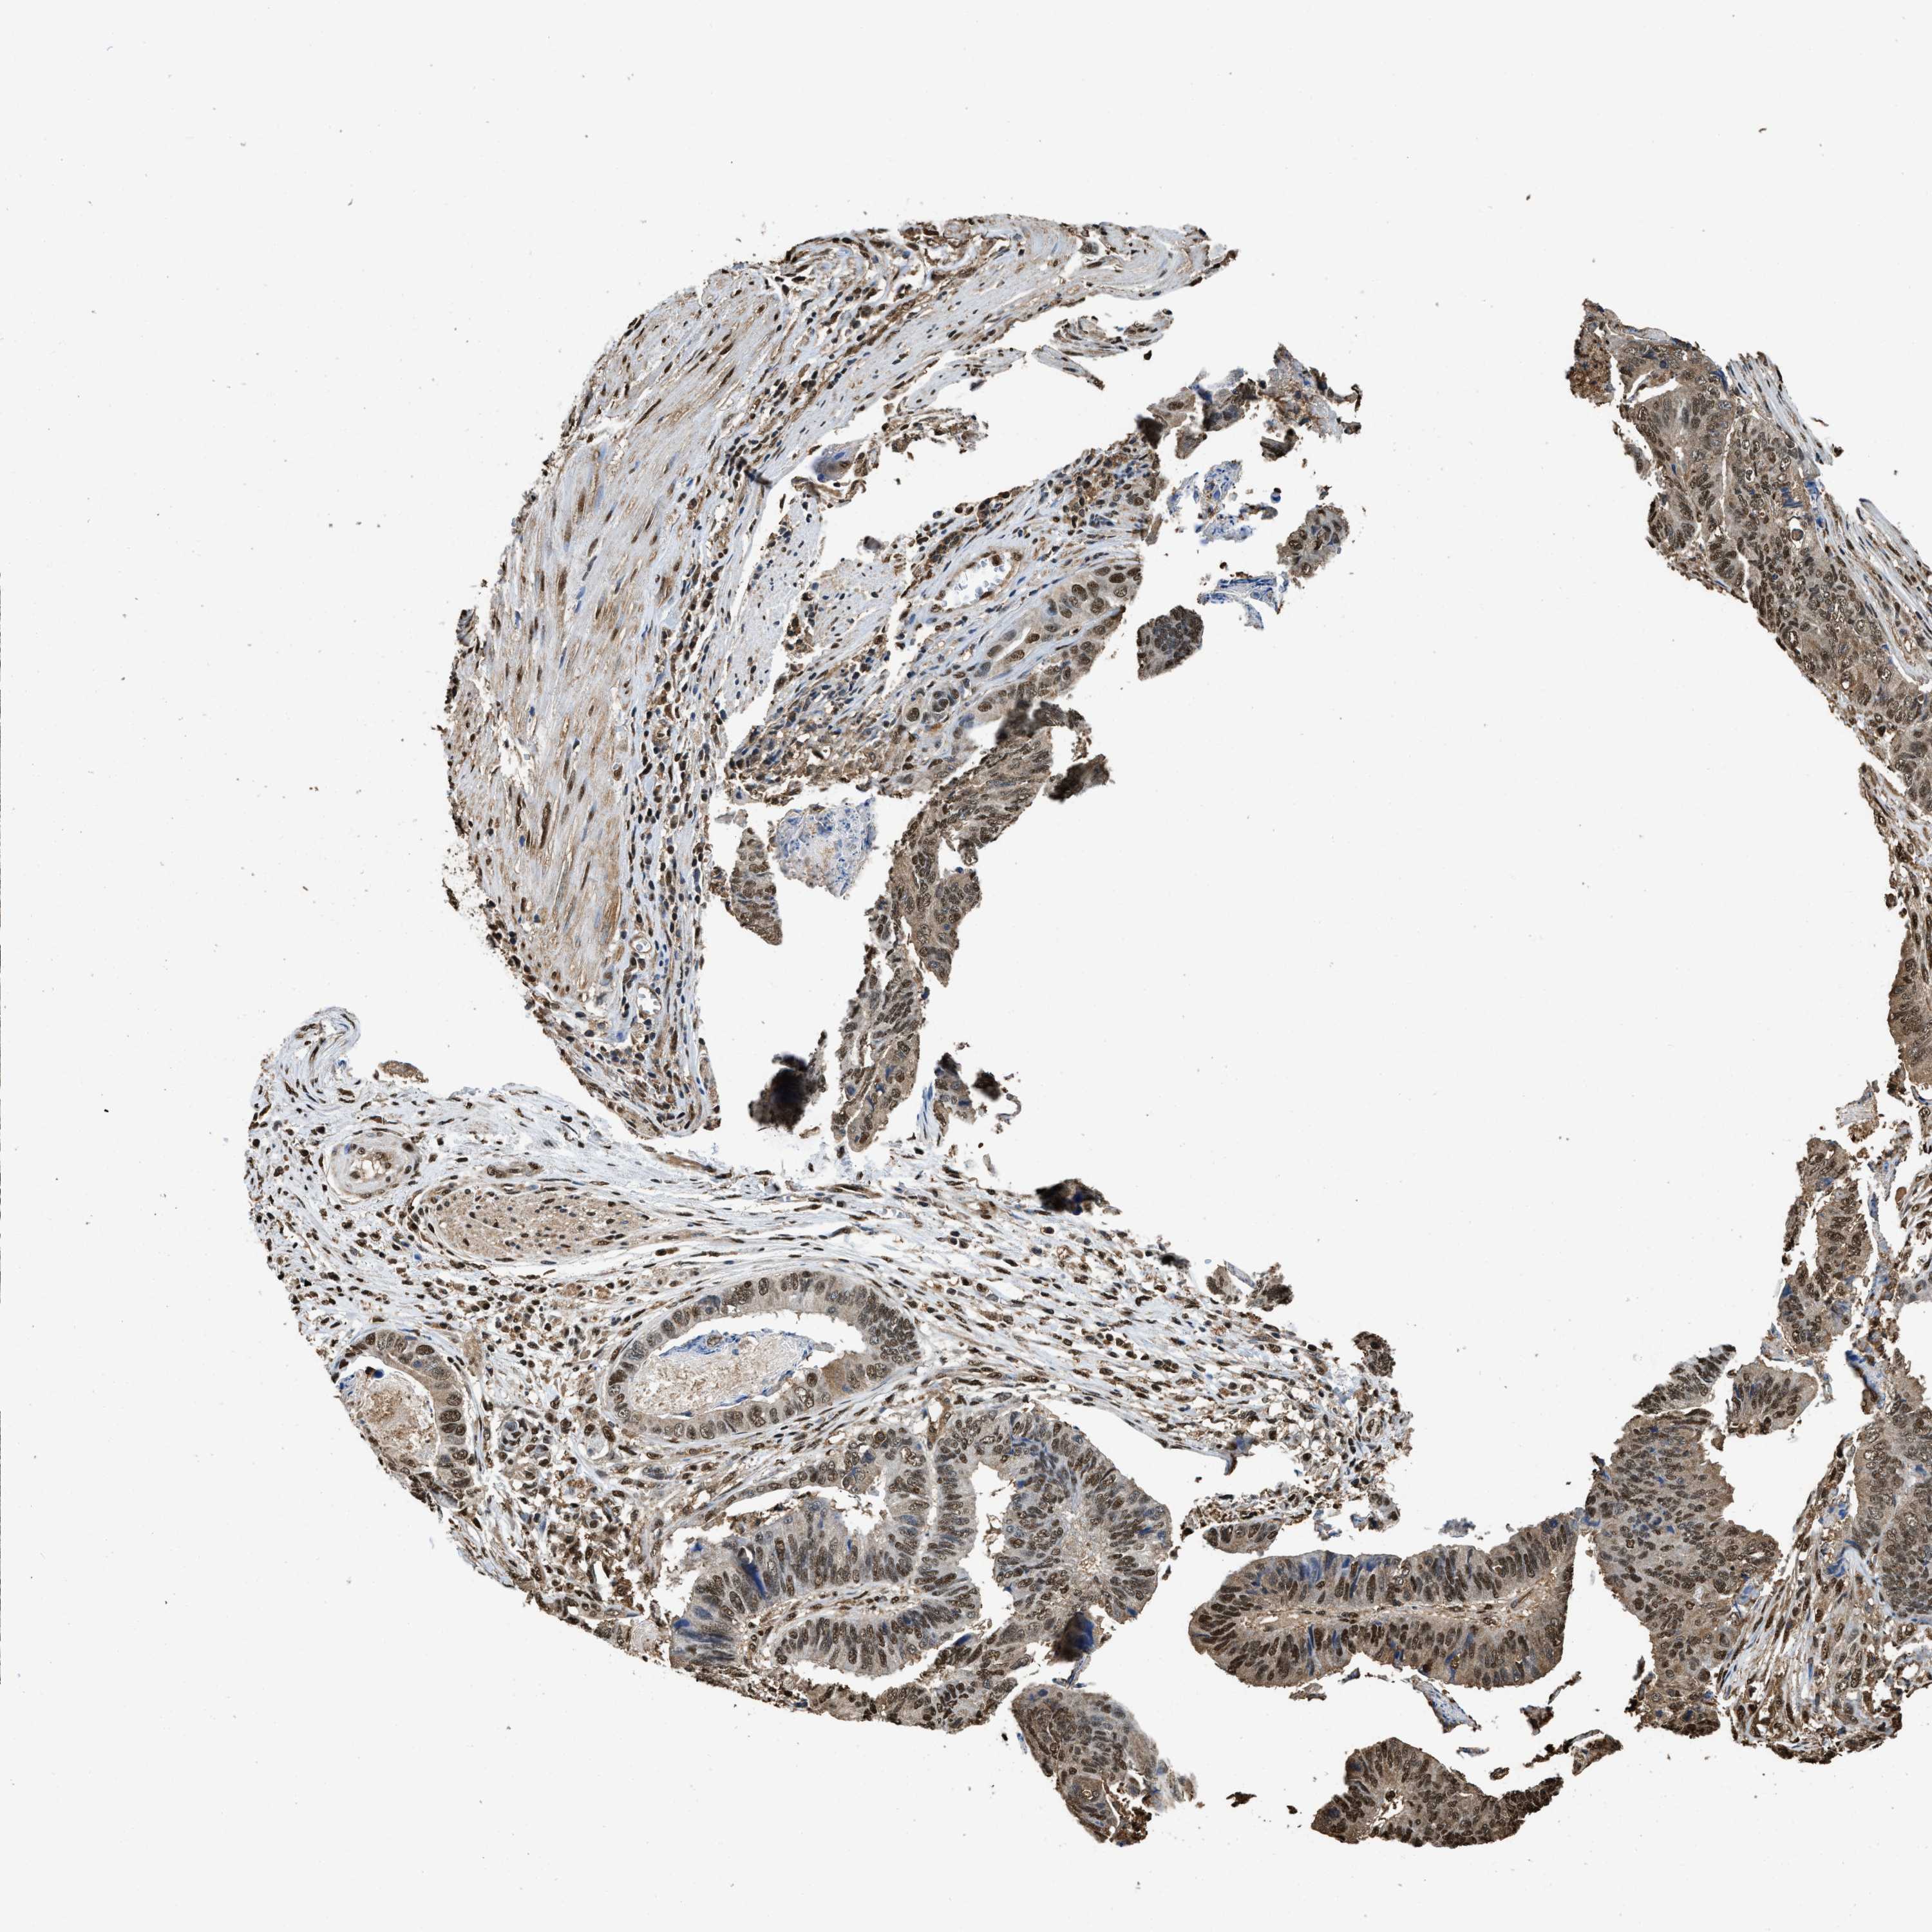

STOMACH CANCER - Protein expressioni

A mouse-over function shows sample information and annotation data. Click on an image to view it in a full screen mode. Samples can be filtered based on level of antibody staining by selecting one or several of the following categories: high, medium, low and not detected. The assay and annotation is described here.

Note that samples used for immunohistochemistry by the Human Protein Atlas do not correspond to samples in the TCGA dataset.

Antibody stainingi

Antibody staining in the annotated cell types in the current human tissue is reported as not detected, low, medium, or high, based on conventional immunohistochemistry profiling in selected tissues. This score is based on the combination of the staining intensity and fraction of stained cells.

Each image is clickable and will lead to virtual microscopy that enables deeper exploration of all samples and also displays staining intensity scores, fraction scores and subcellular localization as well as patient and tissue information for each sample.

Staining

High

Medium

Low

Not detected

Intensity

Strong

Moderate

Weak

Negative

Quantity

>75%

75%-25%

<25%

None

Location

Nuclear

Cytoplasmic/membranous

Cytoplasmic/membranous,nuclear

Adenocarcinoma, NOS

Adenocarcinoma, High grade